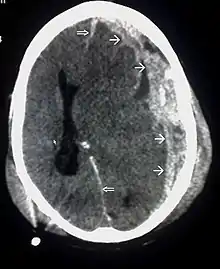

CT scan Spread of the subdural hematoma (single arrows), midline shift (double arrows)

Systems also exist to classify TBI by its pathological features.[67] Lesions can be extra-axial, (occurring within the skull but outside of the brain) or intra-axial (occurring within the brain tissue).[93] Damage from TBI can be focal or diffuse, confined to specific areas or distributed in a more general manner, respectively.[94] However, it is common for both types of injury to exist in a given case.[94]

Hematomas, also focal lesions, are collections of blood in or around the brain that can result from hemorrhage.[24] Intracerebral hemorrhage, with bleeding in the brain tissue itself, is an intra-axial lesion. Extra-axial lesions include epidural hematoma, subdural hematoma, subarachnoid hemorrhage, and intraventricular hemorrhage.[105] Epidural hematoma involves bleeding into the area between the skull and the dura mater, the outermost of the three membranes surrounding the brain.[24] In subdural hematoma, bleeding occurs between the dura and the arachnoid mater.[32] Subarachnoid hemorrhage involves bleeding into the space between the arachnoid membrane and the pia mater.[32] Intraventricular hemorrhage occurs when there is bleeding in the ventricles.[105]